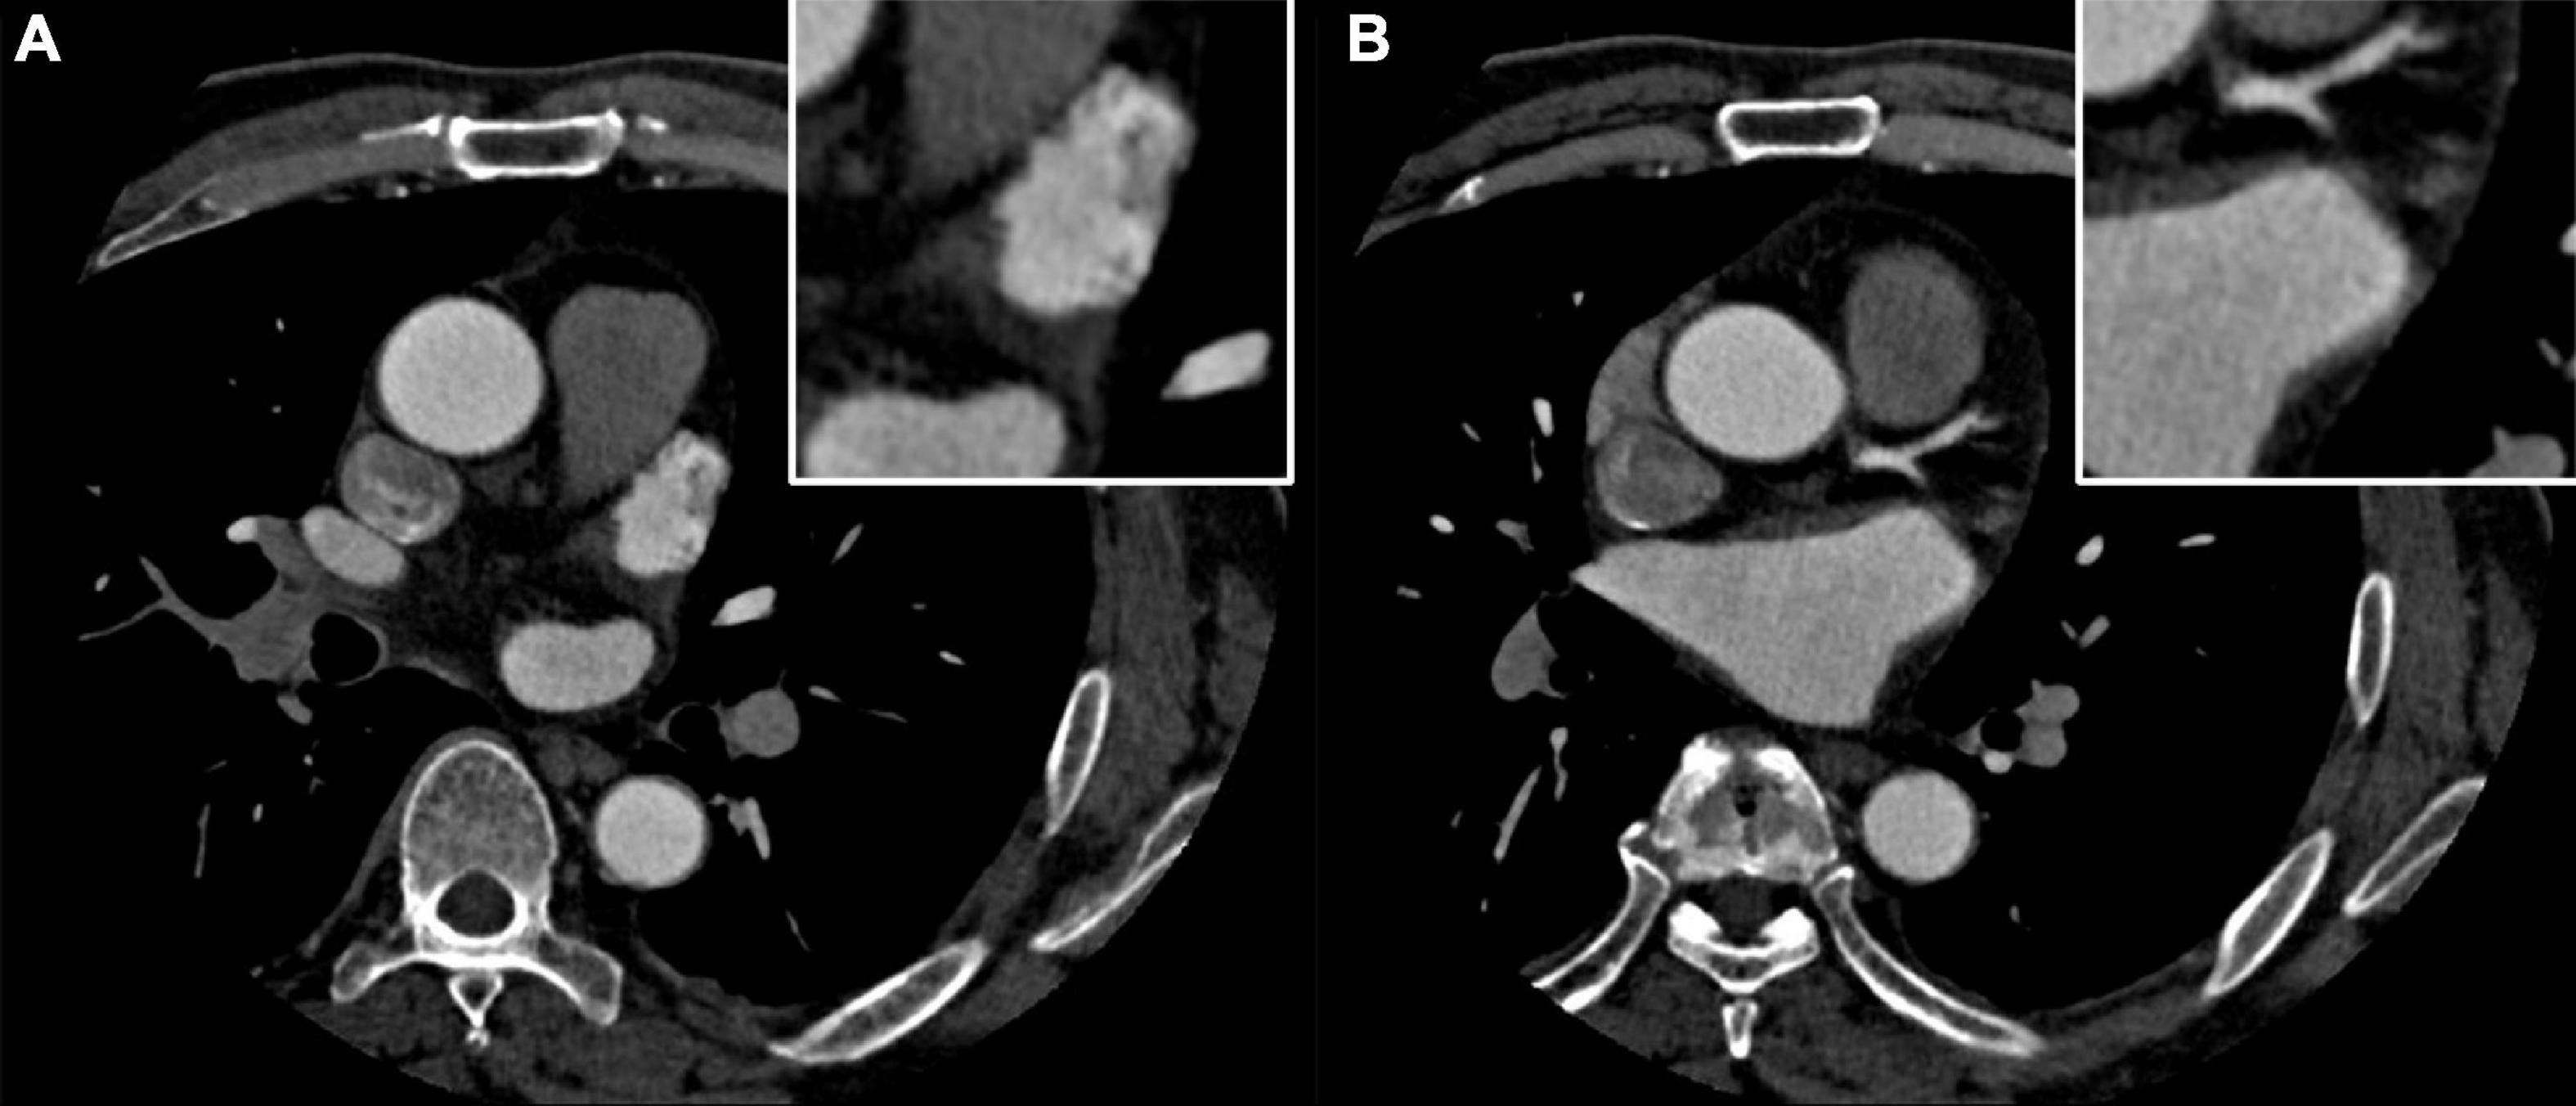

A 58-year-old man was admitted to the cardiovascular department due to palpitation and shortness of breath. He was diagnosed with paroxysmal atrial fibrillation 3 years ago, and no treatment is given. Recent ECG and Holter monitoring confirmed its persistent episode. After being anticoagulated (rivaroxaban 20 mg daily) for 3 weeks, he was admitted and prepared for AF catheter ablation. He had a history of well-controlled hypertension. Physical examination and ECG confirmed the diagnosis of persistent AF. All blood tests and echocardiography were within normal limits, and preoperative left atrium CT angiography demonstrated no intracardiac thrombus (Figures 1A,B).

Figure 1. (A,B) Preoperative left atrium computed tomography (CT) angiography excludes the intracardiac thrombus.